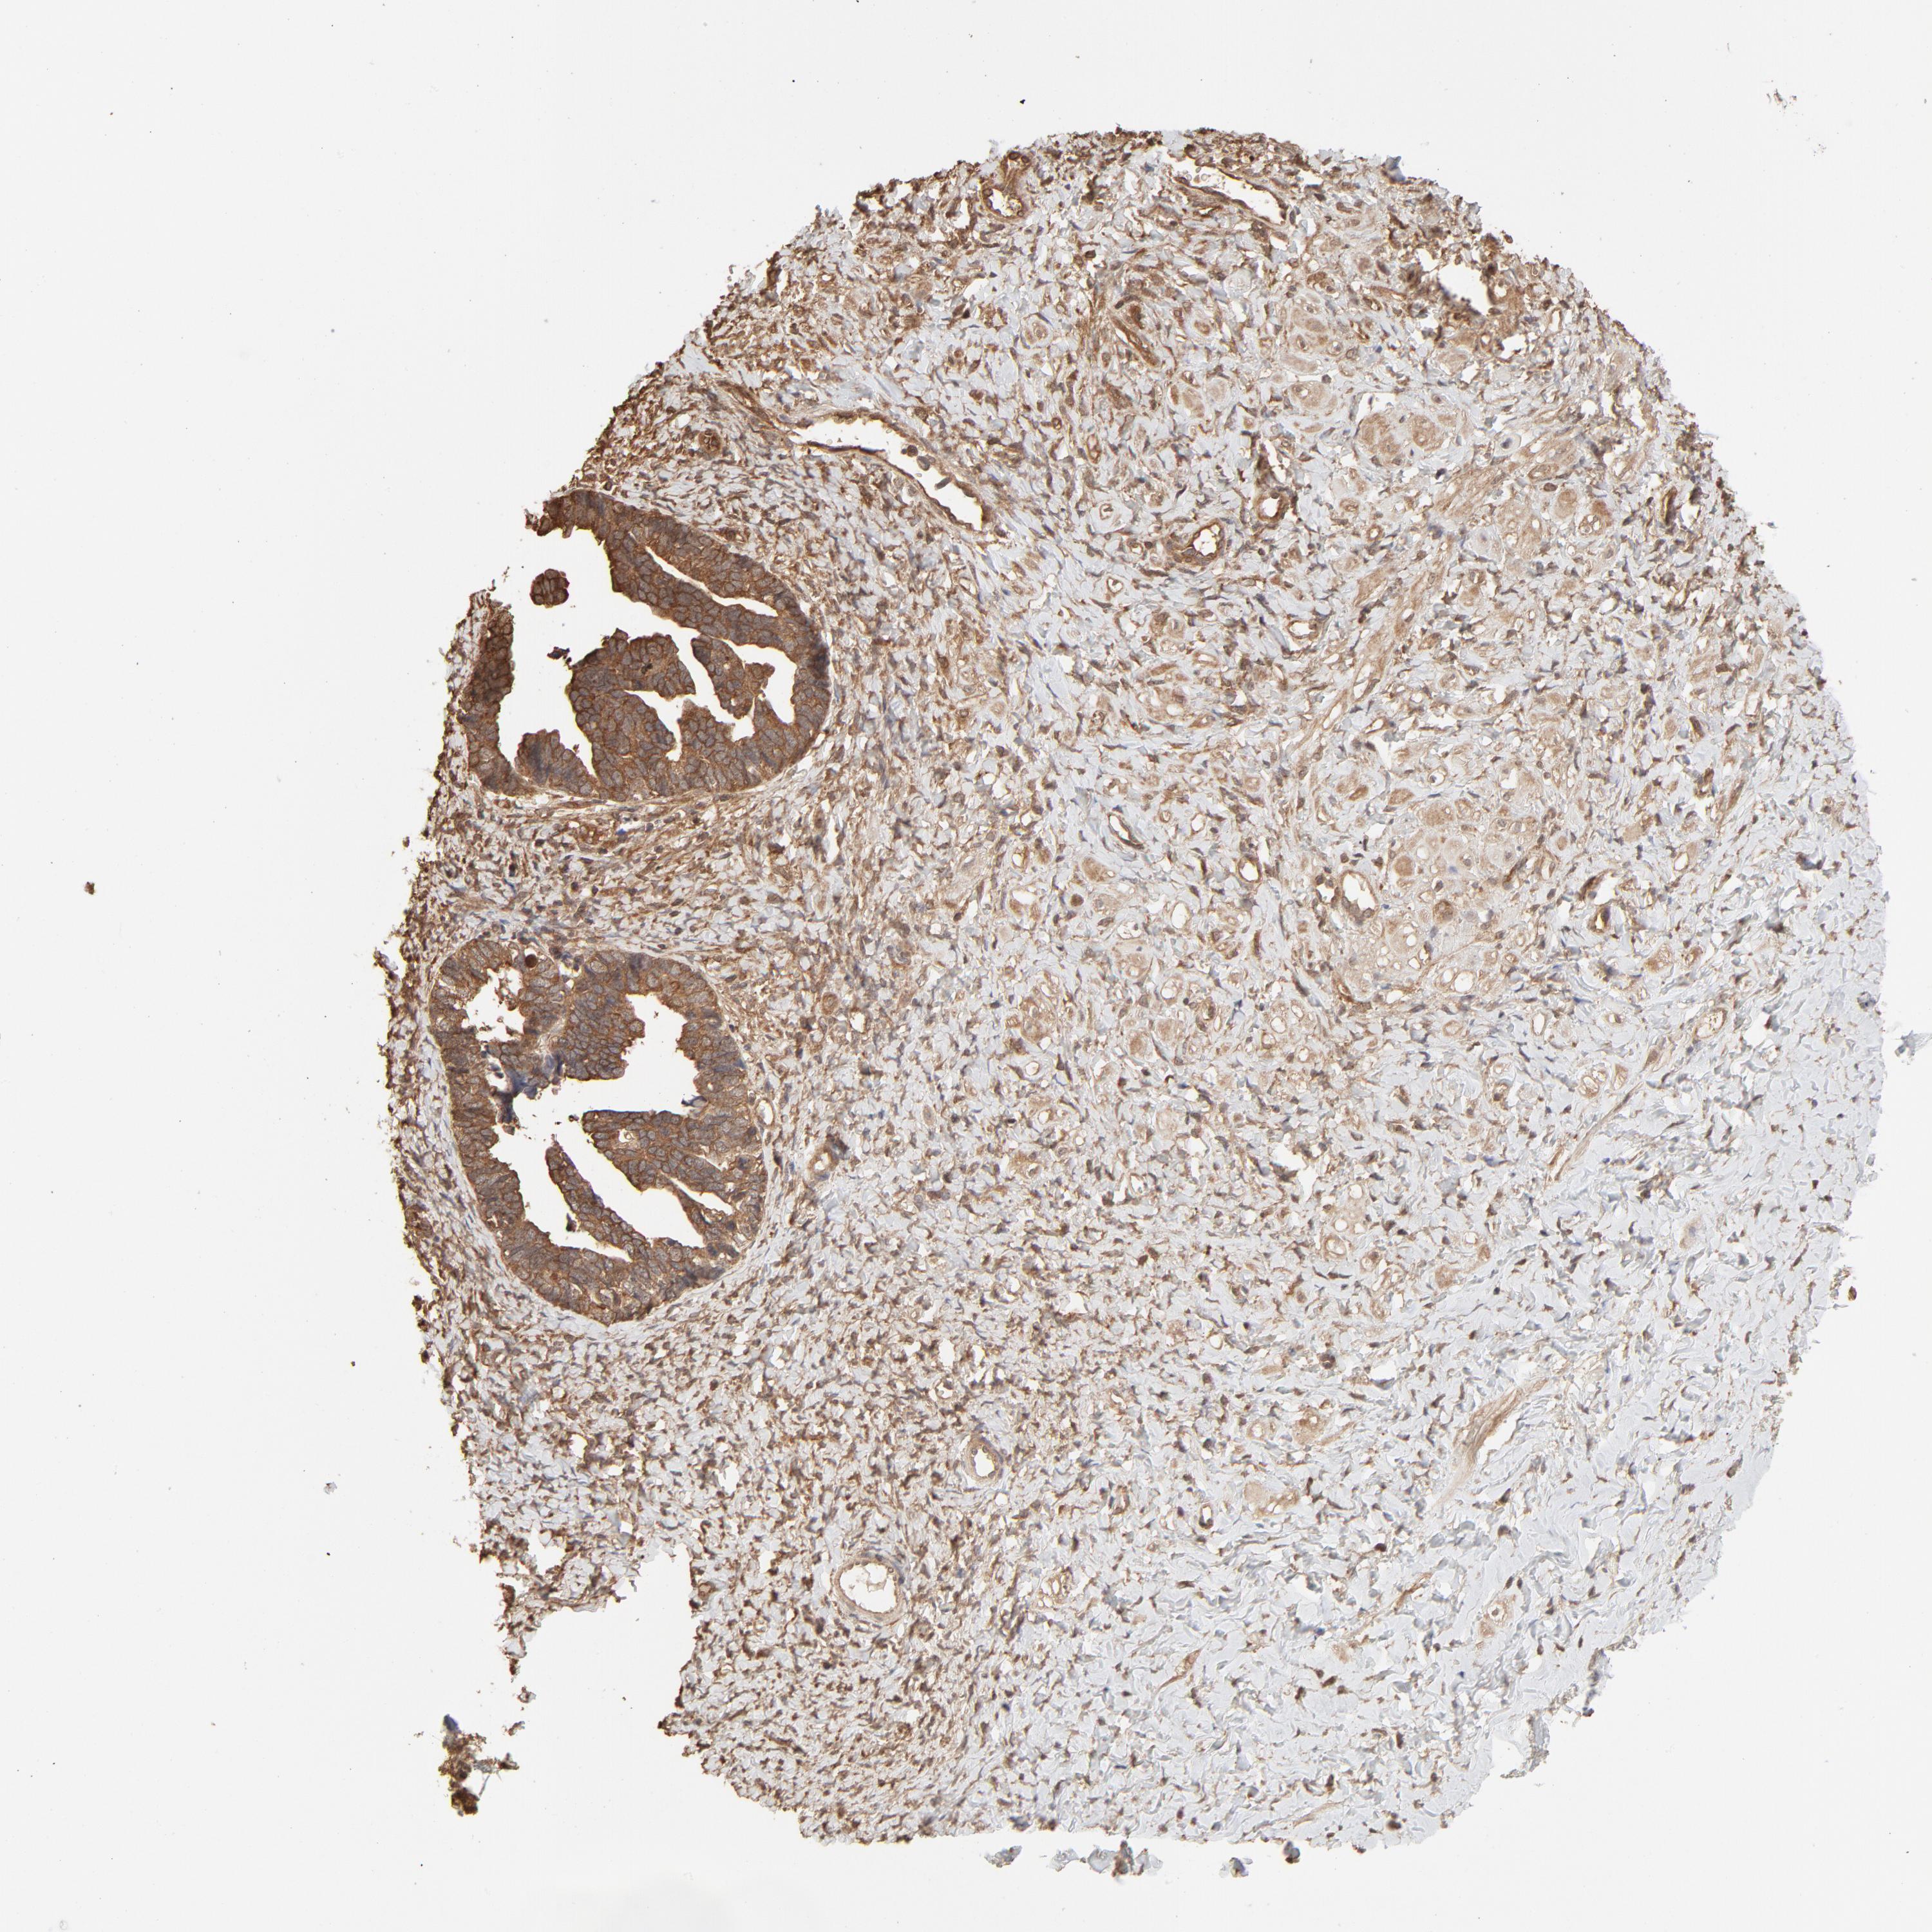

OVARIAN CANCER - Protein expressioni

A mouse-over function shows sample information and annotation data. Click on an image to view it in a full screen mode. Samples can be filtered based on level of antibody staining by selecting one or several of the following categories: high, medium, low and not detected. The assay and annotation is described here.

Note that samples used for immunohistochemistry by the Human Protein Atlas do not correspond to samples in the TCGA dataset.

Antibody stainingi

Antibody staining in the annotated cell types in the current human tissue is reported as not detected, low, medium, or high, based on conventional immunohistochemistry profiling in selected tissues. This score is based on the combination of the staining intensity and fraction of stained cells.

Each image is clickable and will lead to virtual microscopy that enables deeper exploration of all samples and also displays staining intensity scores, fraction scores and subcellular localization as well as patient and tissue information for each sample.

Antibody HPA043236

Antibody CAB003848

Cystadenocarcinoma, serous, NOS

Carcinoma, endometroid

Cystadenocarcinoma, mucinous, NOS

Carcinoma, NOS